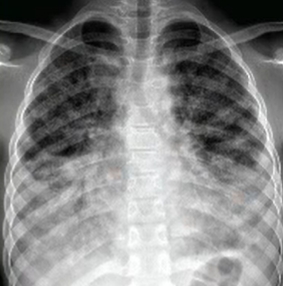

- 손톱 끝이 둥글게 부풀어 오르는 곤봉지

✔ 흉부 CT에서 이상 소견이 나온 경우